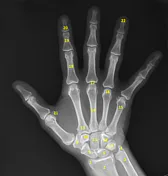

Select the 2nd digit PIP and 4th digit DIP.

Where is the CR centered in this projection?

2nd PIP

3rd DIP

3rd MCP

2nd MCP